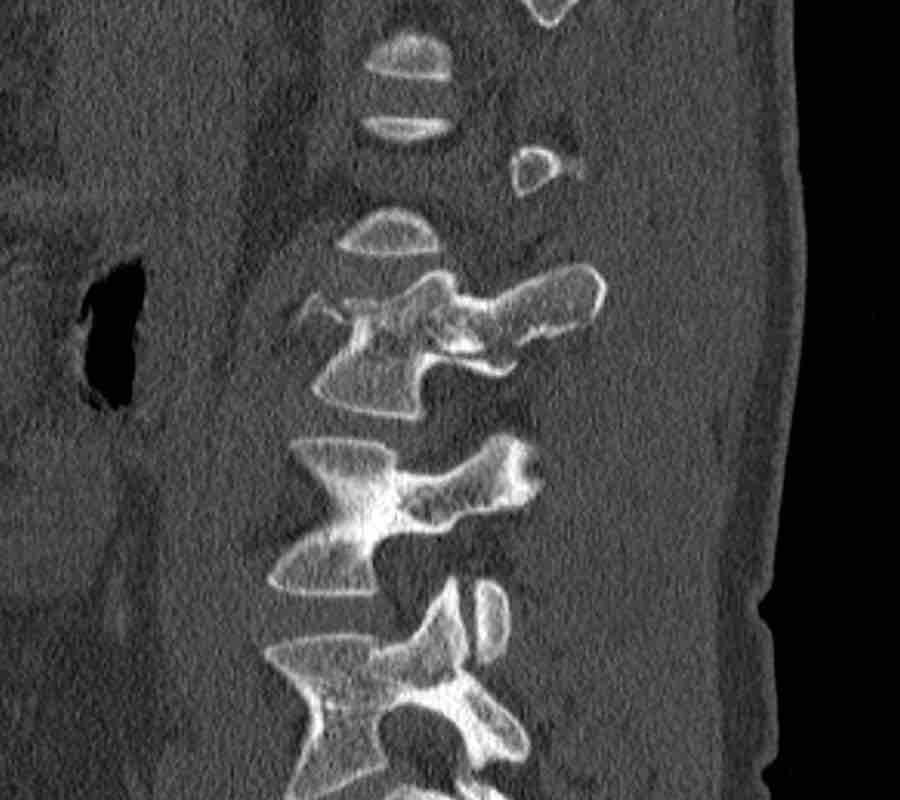

Scroll through the images.

What are the findings?

What is the highest AO-type of injury?

Findings

- Vertical fracture of the posterior border of the vertebral body. It looks a bit odd.

- Again we first have to look for the presence of a type C injury.

- Notice that there is a subtle posterior dislocation of the proximal levels. So this has to be C injury.

Conclusion

Injury type C + A3